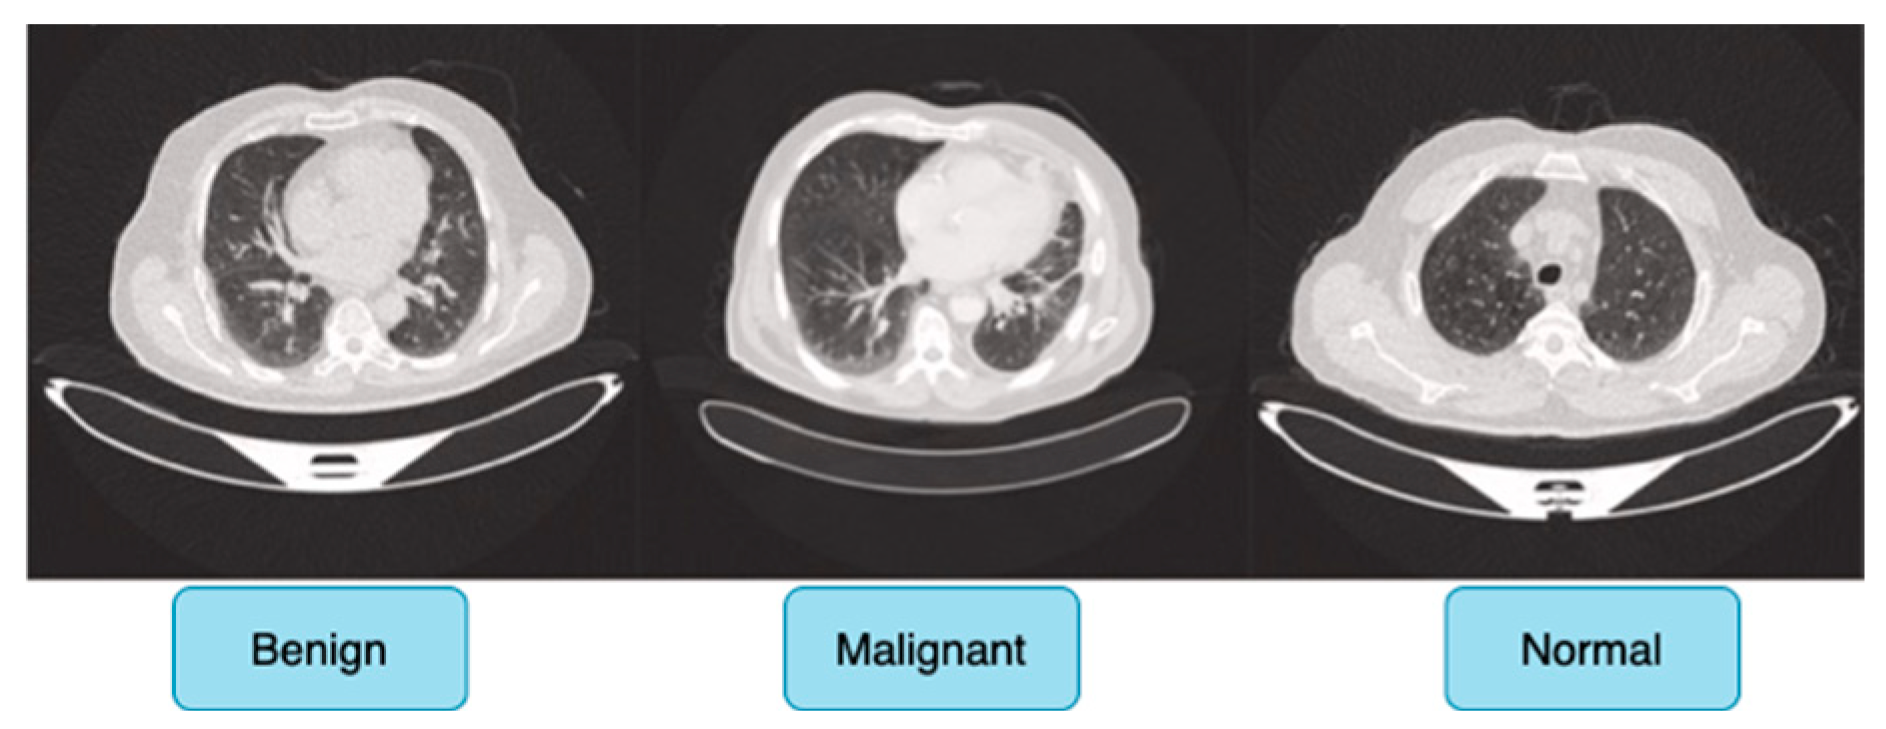

The IQ-OTH/NCCD dataset comprises 1190 CT scan slices from 110 individuals with diverse demographic backgrounds, including age, gender, education level, place of residence, and lifestyle factors, and is categorized into three diagnostic groups: 40 malignant cases, 15 benign cases, and 55 normal (healthy) cases, ensuring a balanced and meaningful distribution for classification tasks.

Figure 6 shows sample images for benign, malignant and normal lung cancer CT images from the dataset.

Originally, the dataset comprised 512 × 512 DICOM CT images; however, to enhance compatibility with deep learning frameworks while preserving medical fidelity, these images were converted to a lossless PNG format. This conversion retains essential radiological features, ensuring the dataset remains suitable for robust feature extraction in deep learning-based cancer detection models. The dataset is publicly accessible via the Kaggle platform, promoting reproducibility and further research advancements [